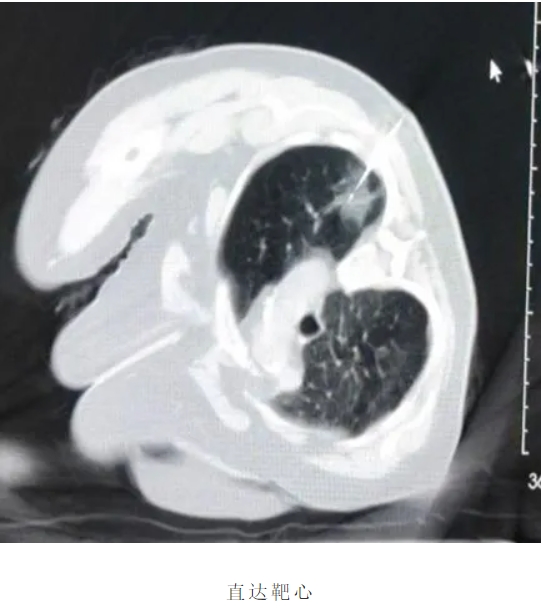

患者老年女性,既往高血压3级很高危、阑尾术后、胆囊结石术后,多种药物过敏史,病灶位于左肺上叶。面对患者高龄、合并多系统疾病等严峻挑战,我院胸外科团队与辽宁省人民医院胸外科专家杨海涛教授深入探讨治疗方案,与患者家属充分沟通后最终决定为患者行微波消融术,术中在CT引导下精准定位靶点。面对患者高龄、合并多系统疾病等严峻挑战,我院胸外科团队与杨海涛教授深入探讨治疗方案,与患者家属充分沟通后最终决定为患者行微波消融术,术中在CT引导下精准定位靶点。

患者老年男性,既往高血压3级、糖尿病、肺气肿,病灶位于右肺下叶。患者微波消融意愿强烈,通过团队积极讨论,在解决结节的同时为后期治疗提供有力依据,术中在CT引导下精准定位靶点,活检、消融一体化。同期解决患者痛点。

- 毫米级精准:依托CT/MRI实时影像融合技术,定位误差小于0.5毫米,避免损伤正常肺组织;